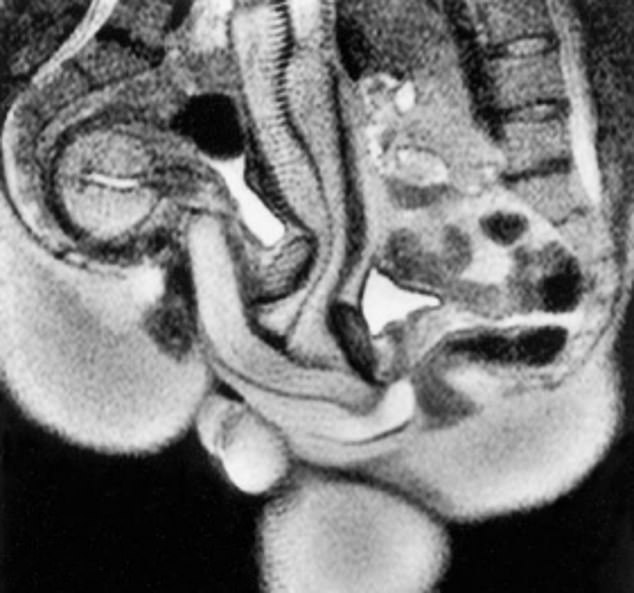

An MRI done in the earlier 20th century on couples having sex showed that the Penis actually curves likes a banana during sex when it is in the Vagina

Pic shown below